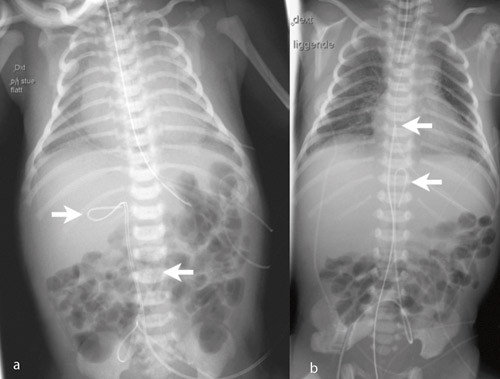

Tabell 1 angir kateterposisjonene. Av navlearteriekatetrene var 45/99 (45 %) primært riktig plassert, og 77/278 (28 %) av venekatetrene. Navlearteriekatetre lå oftere for lavt (44/99; 44 %) enn for høyt (10/99; 10 %) (p < 0,001). Tilsvarende lå flere navlevenekatetre for lavt (126/278; 45 %) enn for høyt (75/278; 27 %) (p < 0,001). Hos 14 (5 %) av venekatetrene og seks (6 %) av arteriekatetrene var det krøll på kateteret (fig 3). For venekatetrene lå krøllen hos 11 i ductus venosus og hos tre i portveneområdet. For arteriekatetrene lå krøllen hos alle i aorta.

Både navlevene- og navlearteriekatetre kan krølles opp hvis spissen fanges av karets intima (fig 3). Økt fare for intimaskade med trombosering kan da foreligge. Krøllen bør rettes ut ved å trekke kateteret tilbake.